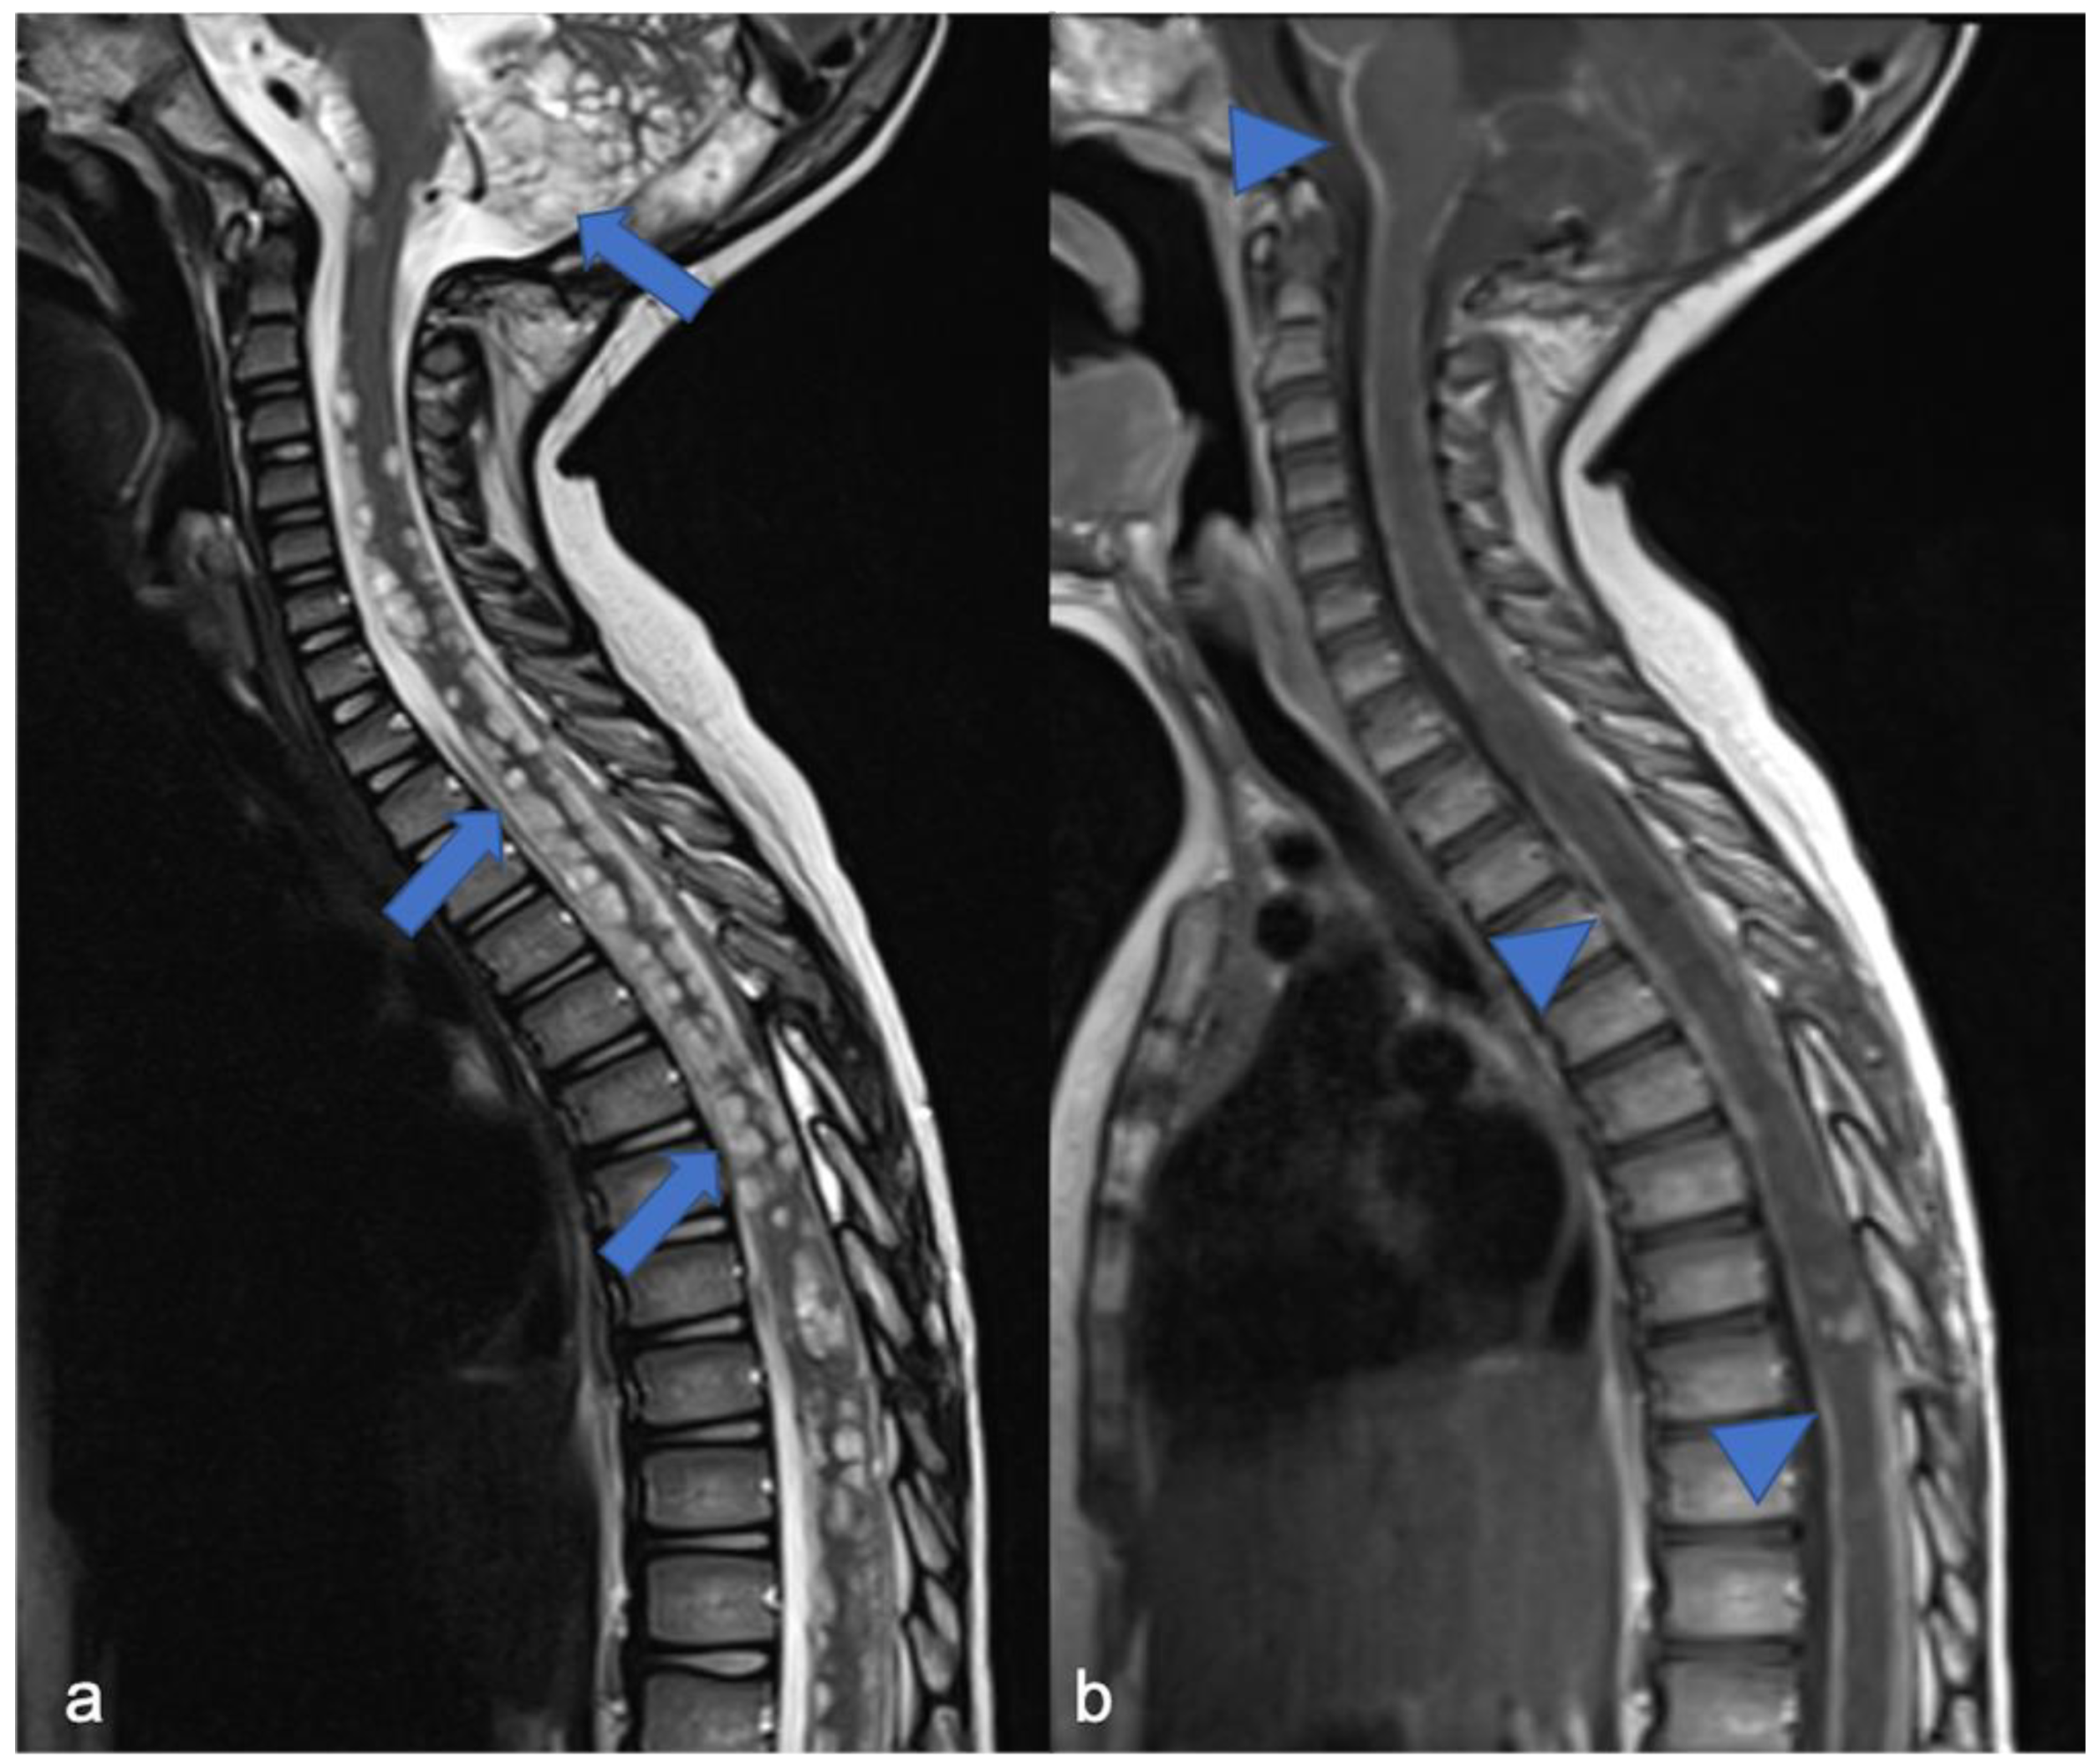

On the other hand, the diagnosis of spinal ependymoma can be linked to neurofibromatosis type 2 (NF2, 1 in 60,000 people [71,80], germ-line mutation in the NF2 gene). Family heredity is recognized in half of the patients with NF2, while in the remaining cases, a “de novo” mutation is hypothesized. NF2 may show schwannoma (typically bilateral vestibular tumors) and cranial/spinal meningiomas and ependymomas [81]. Spinal meningiomas are seen in approximately 20% of patients with NF2 [82,83] and often belong to the fibrous variant [83,84]. In 50% of the patients, the NF2 manifestations occur from the second decade of life; however, related to the type of genetic alteration, two clinical subtypes are recognized. The Wishart phenotype (Figure 12) is associated with more severe diseases, tumors onset before the age of 20, rapid progression, and truncating alterations in NF2 gene, while the Gardner phenotype shows milder disease, later and slower onset of tumors, and missense loss-of-function mutations in the NF2 gene [83,85].

Figure 12.

A detail of the lumbo-sacral spine in a twelve-year-old child with NF2 and Wishart phenotype. Sagittal T2-weighted (a) and post-contrast T1-weighted (b) images show an expansive intramedullary lesion of the cauda, hyperintense in T2 (arrows) with enhancement. These findings are compatible with ependymoma in patient with NF2.